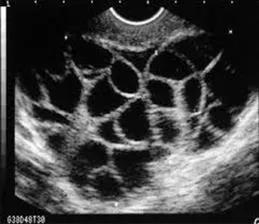

(卵巢全是卵泡)

这样的情况在医院中并不少见。四川大学华西医院甚至专门有一个科室收治卵巢过度刺激综合征的患者。